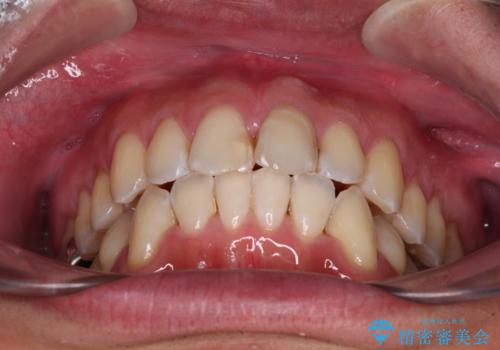

下顎にワイヤー装置を装着し、暫くしたところでやはりインビザラインにて矯正治療をしたいとのことで、インビザラインに切り替えました。

短い期間でしたがワイヤー装置を使用したことでデコボコが解消されたため、インビザラインの比較的短い期間で矯正治療を行うことができました。